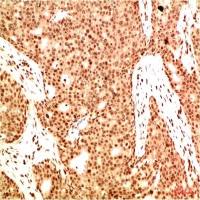

乙酰化抗体